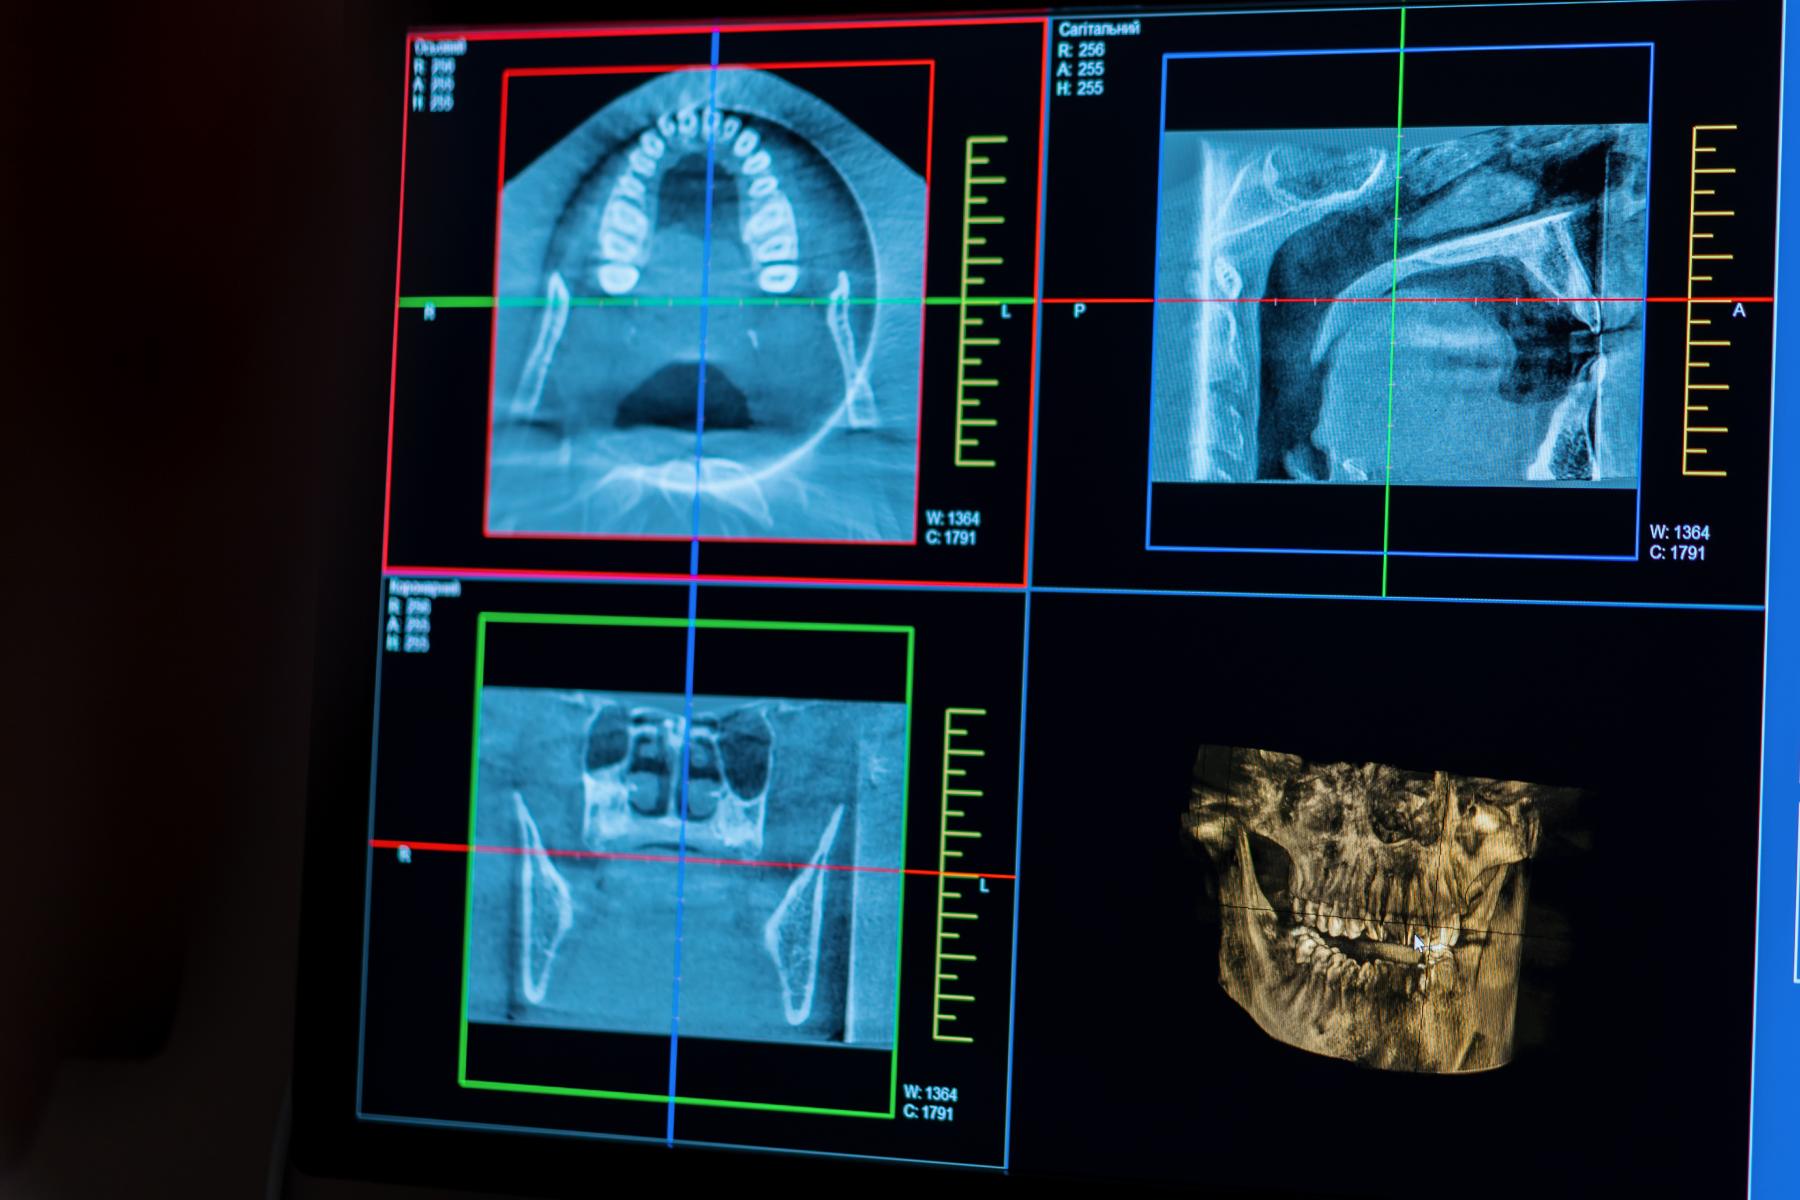

Radio panoramique 3D

La radio panoramique 3D permet d’obtenir une vue complète des dents et des mâchoires. Cet examen rapide aide à poser un diagnostic précis et à planifier les traitements, notamment en implantologie ou en chirurgie orale.